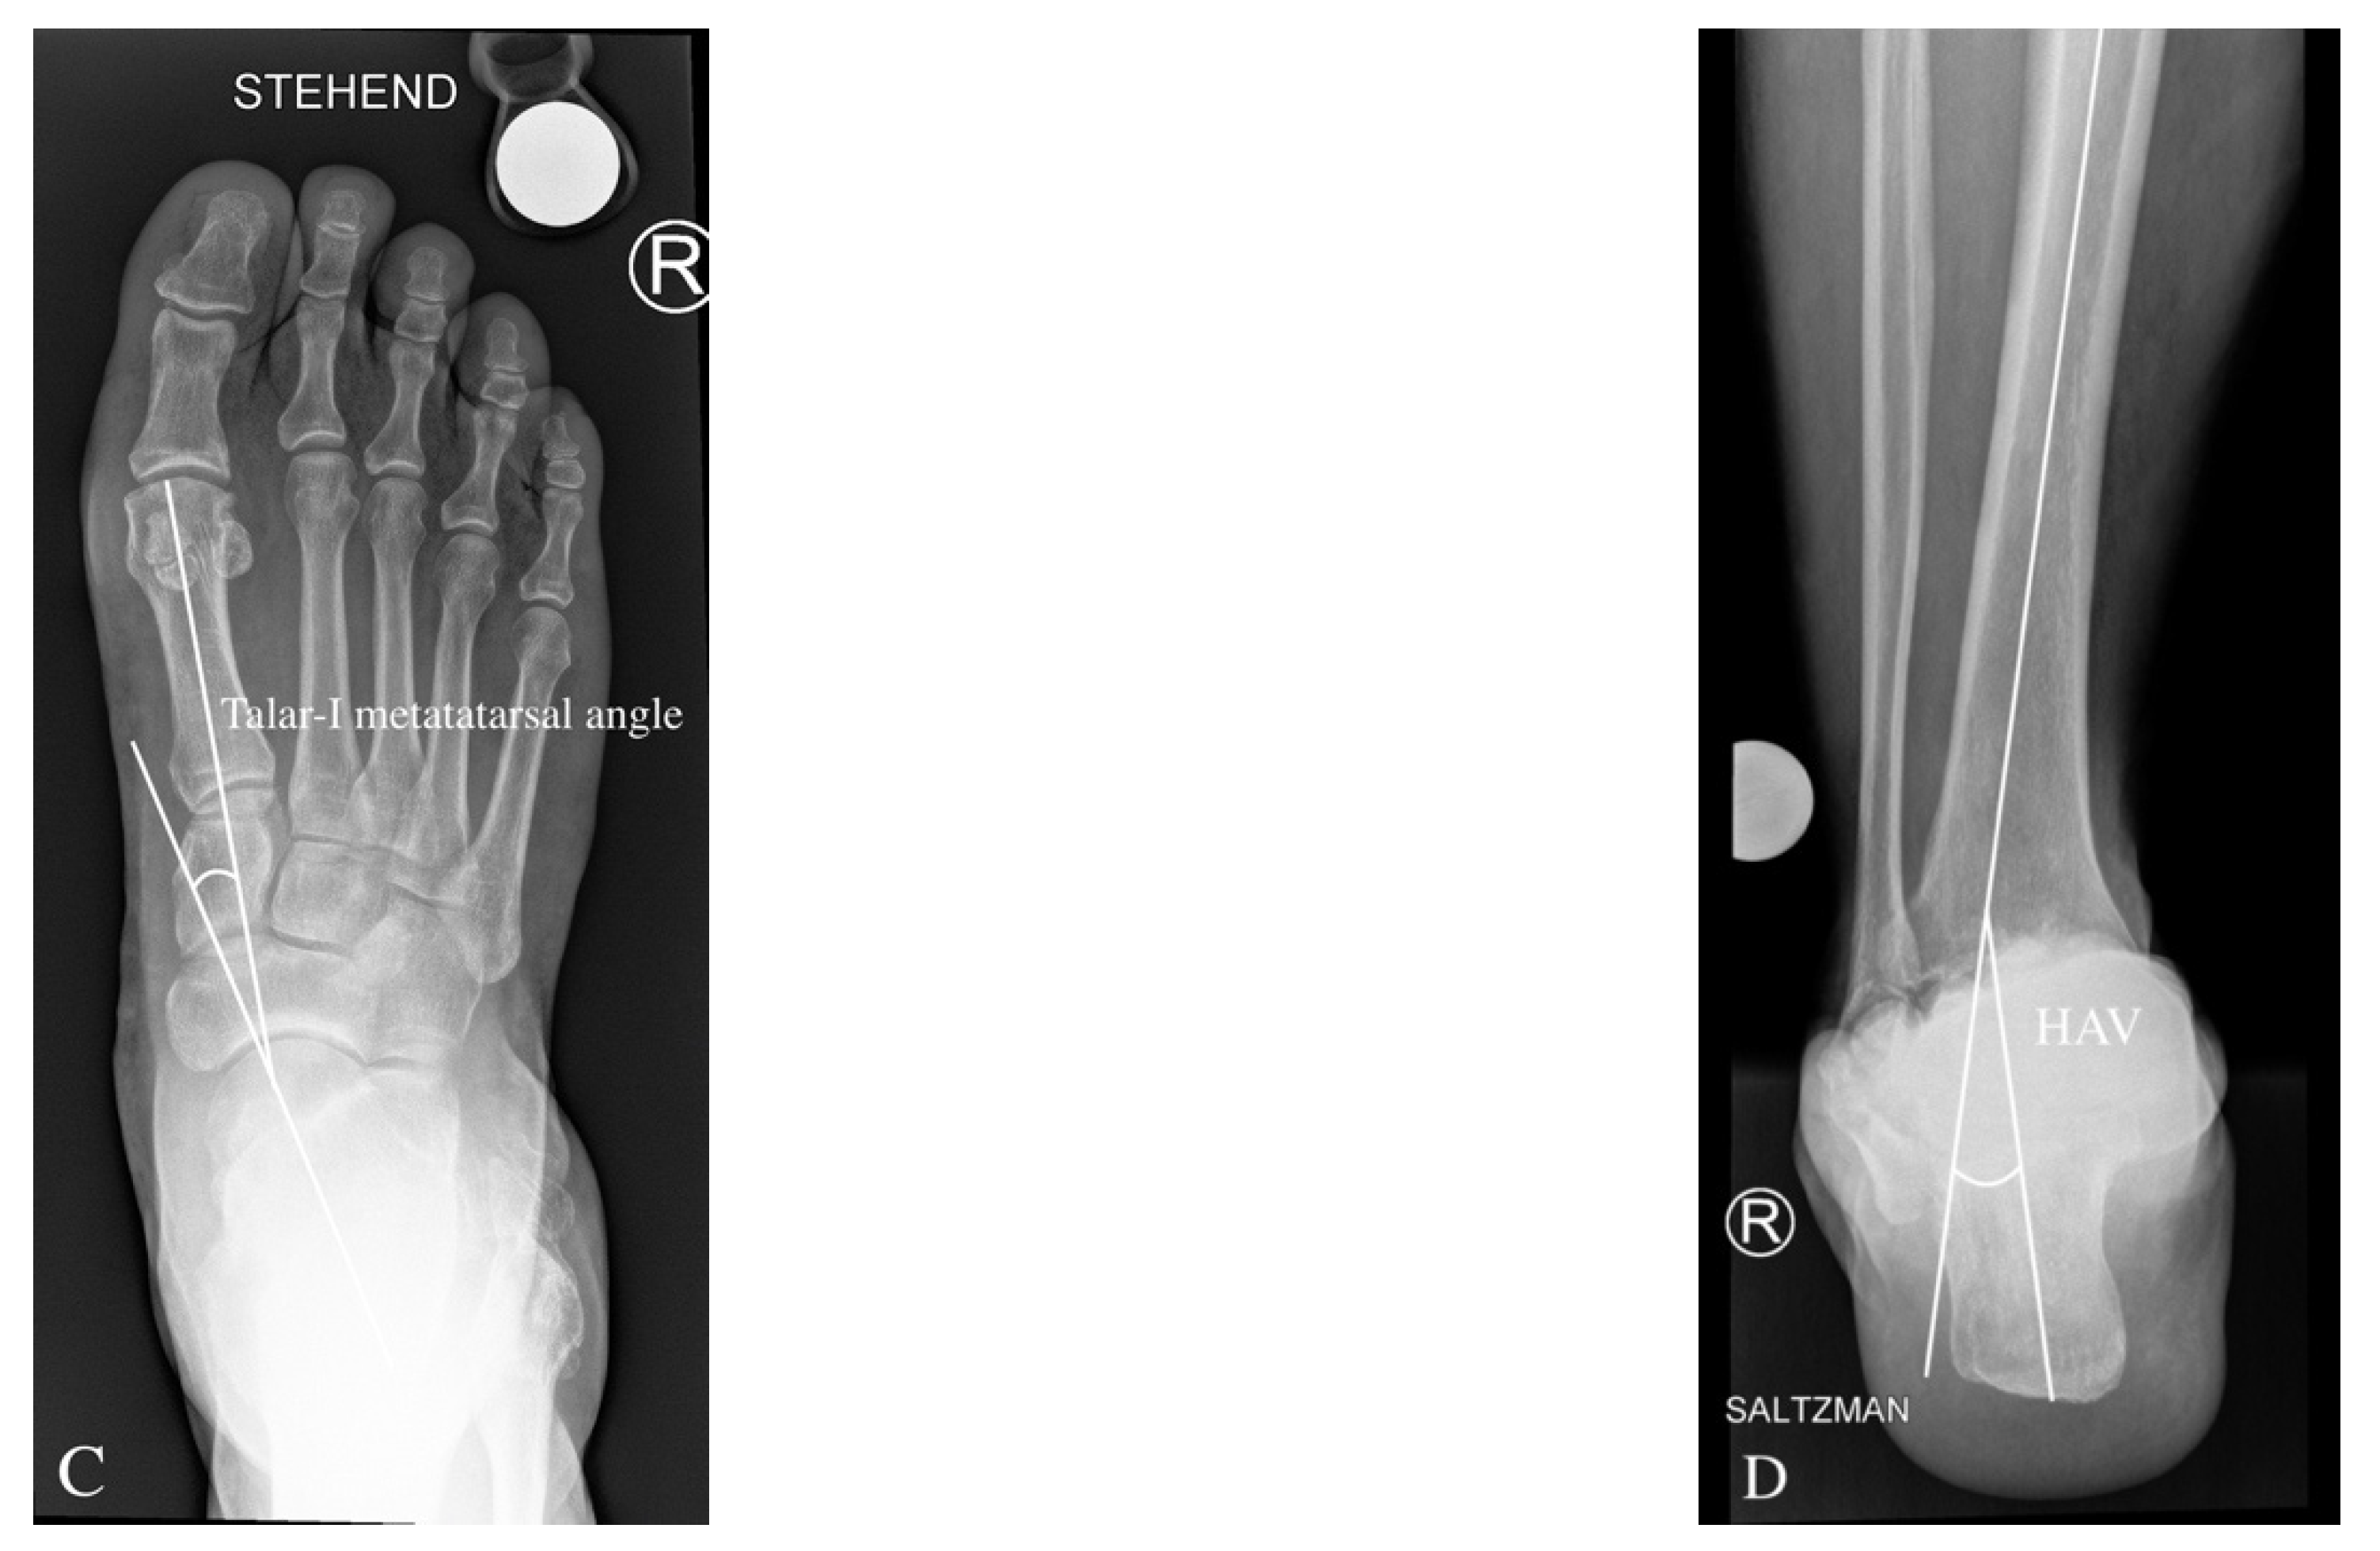

3.2. Preoperative Radiological Angle Measurements